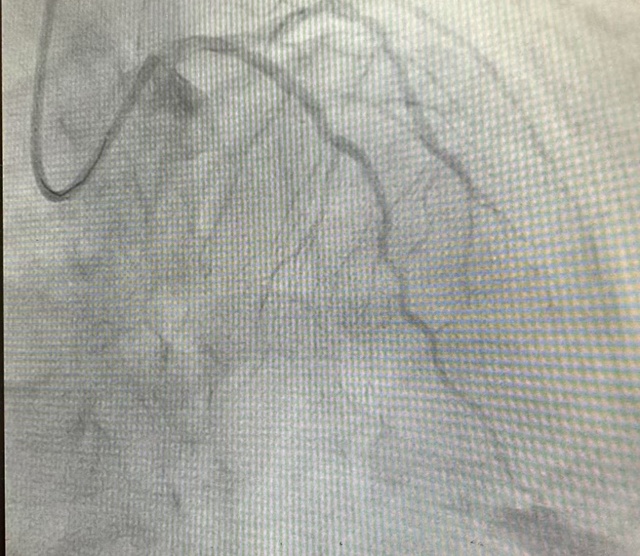

前降支病变血管术前术后图像对比

前降支(LAD)是心脏最重要的供血血管之一,被称为“生命的主干道”。心脏康复科团队在细致评估后,决定采用冠脉支架植入术为王大爷进行治疗。术中通过桡动脉入路,将导丝精准送至LAD病变部位,利用球囊扩张狭窄处后,成功植入一枚药物涂层支架。支架释放后,血管狭窄处立即得到扩张,完善造影示支架贴壁良好,TIMI 血流三级。手术全程仅用时40分钟,创伤小、恢复快。术后患者胸闷、憋气症状显著缓解,生活质量大幅提升。